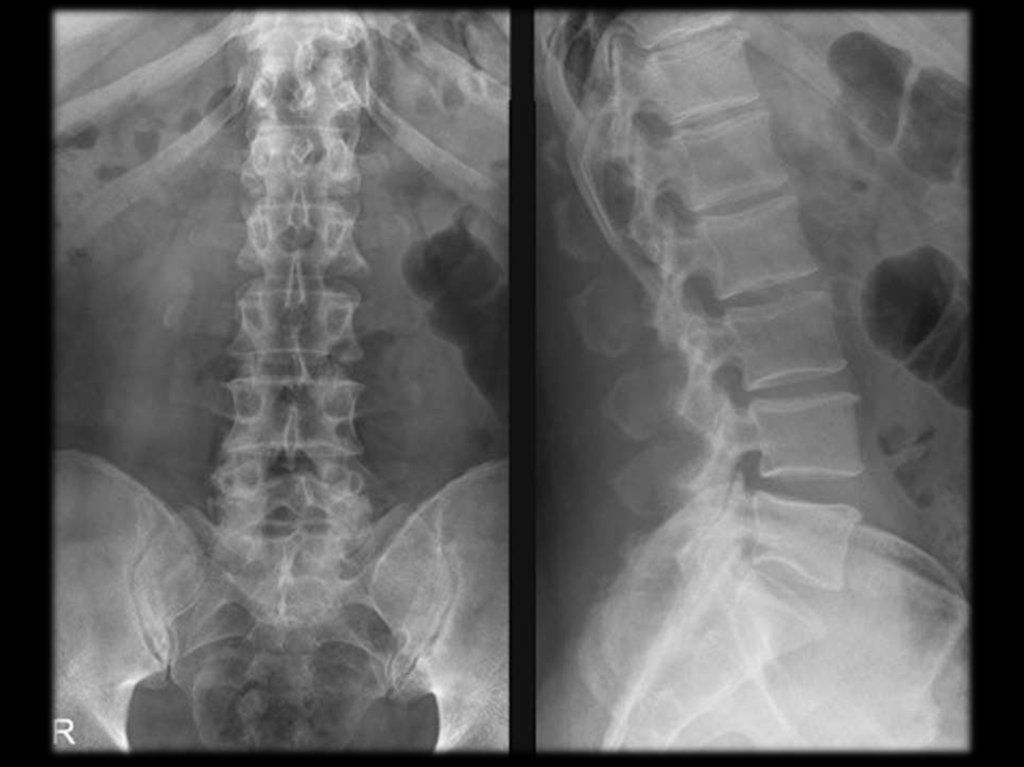

Остеохондроз – уменьшение высоты диска.

Спондилёз – краевые костные разрастания.

Спондилоартроз – уменьшение высоты дисков

ведёт к повышению нагрузки на фасеточные

(межпозвонковые) суставы с развитием в них

таких же изменений как при остеоартрозе

периферических суставов.

Спондилолистез – смещение тела вышележащего